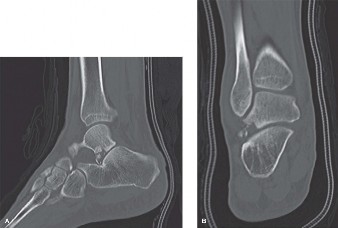

Computed Tomography (CT) Scan:

- Strongly recommended for complex fracture patterns (e.g., trimalleolar, pilon fractures) to delineate articular involvement, fracture comminution, and the presence of osteochondral fragments.

- Highly valuable in identifying potential soft tissue interposition pre-operatively, though EDB interposition might not always be clearly evident.

- Provides a 3D understanding of the deformity and helps plan implant placement.